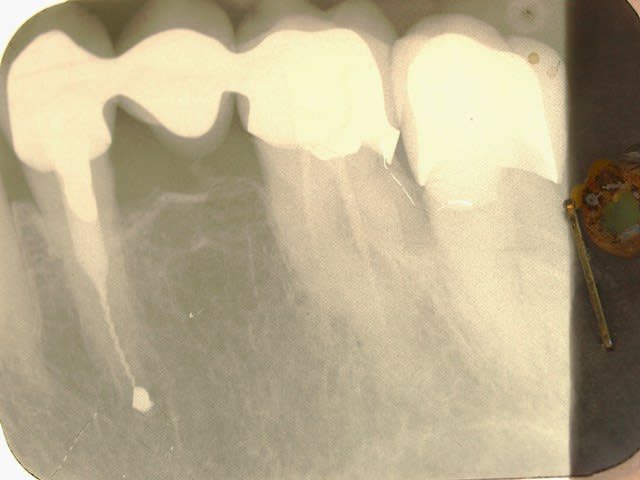

Euh .......les gas y a pas un truc qui vous gêne là ? Vous avez vu les radios ?

Premièrement il faudra que m'expliquer comment le bridge qui au départ est infiltré voir carié sur la 4 se retrouve comme par magie ré-adapté.

Le tenon n'est pas le même

Le traitement endo n'est pas le même

La 7 est couronnée (cantilever) sur une radio , pas sur la radio pré-op

Le niveau osseux n'est pas le meme sur les 2 radios

BREF IL NE S'AGIT PAS DU MEME PATIENT....

Tu dis avoir démonté le bridge et reposé tel quel , ce qui est faux au vu de la radio pré-op en page 5..... le tenon , ete le trt endo sont différents .

Tu as donc inventé une technique pour réadapter des prothèses non adaptées ....... le hyatus a disparu comme par magie , donc 2 possibilités :

- Tu as refait le bridge et tu ne le dis pas

- La radio pré-op est de quelqu'un d'autre

Les autres radios je m'en fous , je dis juste qu'entre les deux radios (15 ans) il y a du y avoir une intervention divine ....

Je te trouve bien hargneux sur ce bridge, parce que si tu regardes bien les radios tu vois bien que c'est le même patient quand-même, et que la 7 a été couronnées par la suite. Les radios ont une incidence un peu différente.

Si 15 ans sépare la radio pré opératoire de la dernière radio, force et de constater que la réimplantation a fonctionné.

Je note néanmoins une cratérisation apparue autour de la partie cervicale de la racine réimplanté, suite à l'intervention, mais stabilisée par la suite.

Mais globalement, il est indéniable que la réimplantation a marché, et qu'une intervention chirurgicale à rétro n'aurait pas permis d'obtenir un meilleur résultat.